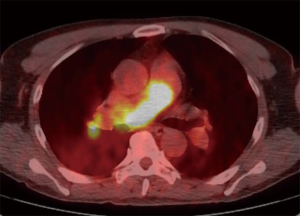

A 58-year-old man was referred to our hospital with a fever and dyspnea on exertion. Enhanced computed tomography showed low-attenuation filling defects occupying the entire luminal diameter of the right main PA, peripherally extending into the right interlobar PA (Figure 1). Positron emission tomography demonstrated an intense uptake of florine-18 fluorodeoxyglucose in the intraluminal defects, with a maximum standardized uptake value of 15.2 (Figure 2). A pulmonary angiogram showed severe stenosis of the right main PA (Figure 3). Right heart catheterization revealed a severely elevated systolic right ventricular pressure of 76 mmHg. Pulmonary function tests showed a mild restrictive ventilatory disorder with vital capacity of 3.05 L (79.6% of predicted value) and forced expiratory volume in 1 second of 2.20 L (70.1% of predicted value). The patient’s condition rapidly deteriorated and he became bed-bound. Based on these findings, PA sarcoma was clinically suspected, and the initial surgical strategy consisted of pulmonary endarterectomy and right pneumonectomy, followed by reimplantation of the right lower lobe in order to preserve the post-operative pulmonary function. All procedures performed in this study were in accordance with the Helsinki Declaration (as revised in 2013). Informed consent was obtained from the patient for publication of this manuscript and any accompanying images.